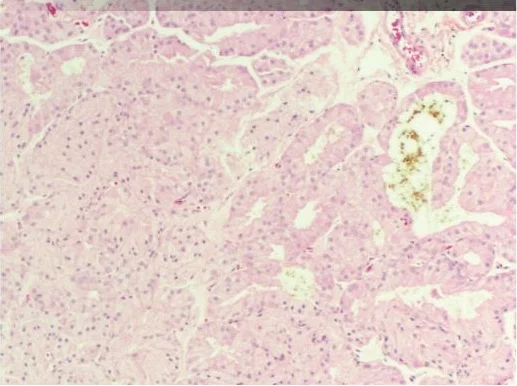

Histological examination

Histological examination revealed severe atrophy of the salivary glands, the exorbital lacrimal glands and Harderian glands.

Our histological examination demonstrated viral inclusions in multiple tissues; most notably, within epithelial cells of the respiratory tract and salivary glands.